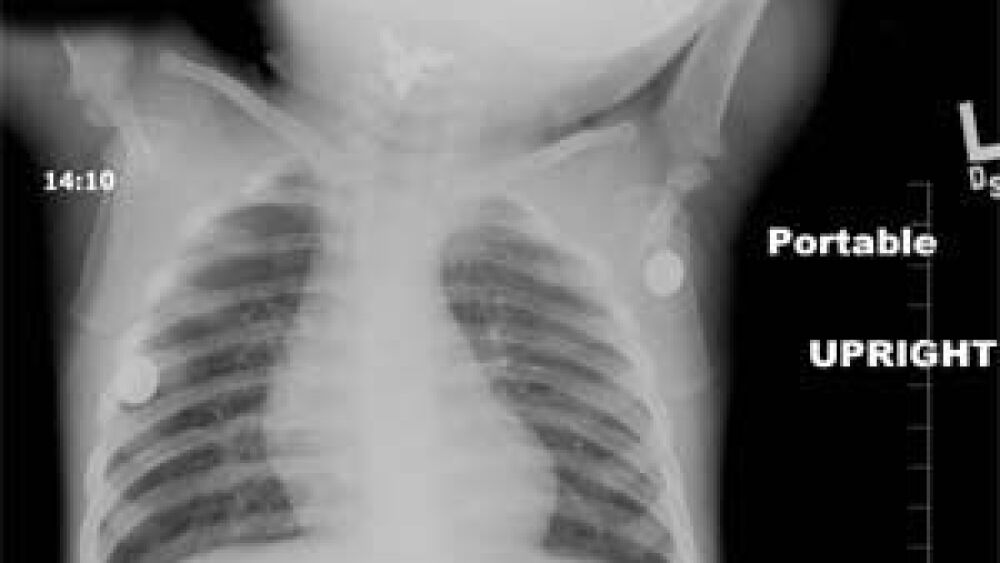

I ordered a quick chest X-ray as we were getting prepared, and that cinched the diagnosis. A metallic foreign body was found in the pharynx, near the area of the epiglottis.